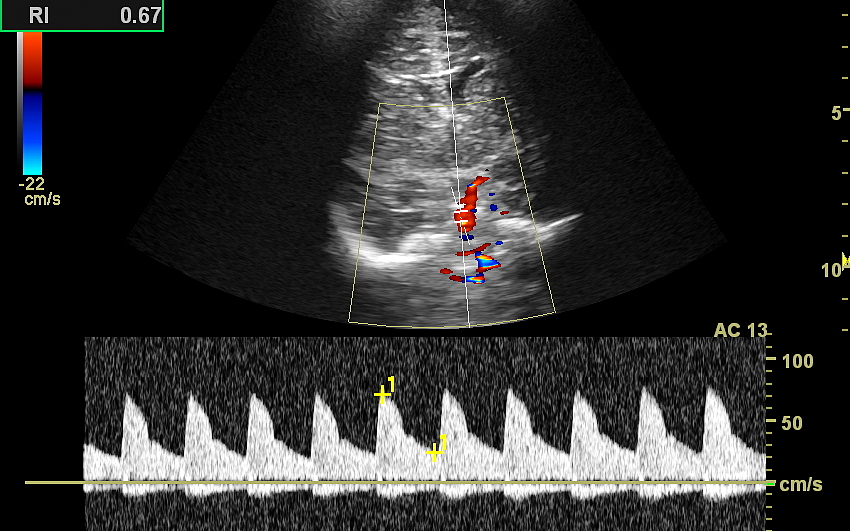

W USG główki dziecka oceniane są struktury wewnątrzczaszkowe, tj. mózg wraz z jego układem komór wewnętrznych, sploty naczyniówkowe, istota biała mózgu i obszary jąder podstawy mózgu, morfologia zakrętów i bruzd mózgowia, przestrzeń przymózgowa, a w trybach dopplerowskich wybrane naczynia tętnicze i żylne mózgu, w tym zatoki żylne. Oceniane są również cechy ciśnienia śródczaszkowego. W opisie badania podawane są również wymagane przez neurologa tzw. wskaźniki komorowe oraz wymiary wybranych struktur.